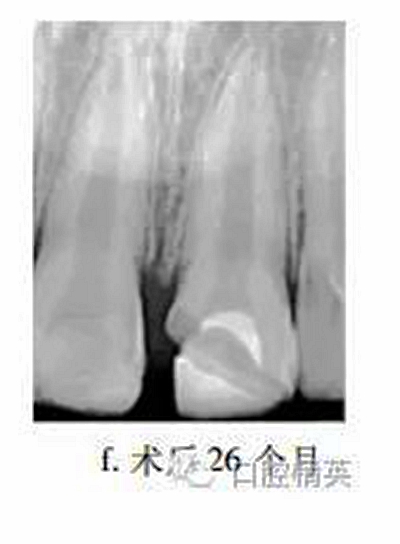

26個月后復(fù)查,患牙無不適,牙髓活力測試較正常牙齒略低,冠部充填物部分脫落,X線片示:患牙蓋髓劑下方可見連續(xù)薄層高密度影像,髓腔縮窄,根尖孔聚攏,牙根長度較鄰牙無明顯差異(圖f)?;佳廊コ糠植Aщx子水門汀,備釘?shù)?,隔濕,納米樹脂修復(fù)冠缺損,調(diào)牙合拋光。

眾多臨床研究表明,MTA用于活髓切斷術(shù)的臨床療效優(yōu)于傳統(tǒng)的蓋髓劑氫氧化鈣,除去MTA較氫氧化鈣具有更好的封閉性以外,低細(xì)胞毒性是其另一重要特點(diǎn)。MTA體外實驗中可促進(jìn)正常牙髓細(xì)胞的牙向分化能力,亦能提高成骨細(xì)胞的體外骨向分化能力。有學(xué)者發(fā)現(xiàn)早期炎癥狀態(tài)下,牙髓干細(xì)胞的體外增殖與成牙能力降低,而成骨能力上調(diào),本病例26個月復(fù)查X線片中發(fā)現(xiàn)MTA下方有薄層連續(xù)高密度影像,牙根伸長,根尖孔聚攏,提示創(chuàng)傷暴露后的牙髓(干)細(xì)胞在MTA誘導(dǎo)下,具有較強(qiáng)的修復(fù)能力。